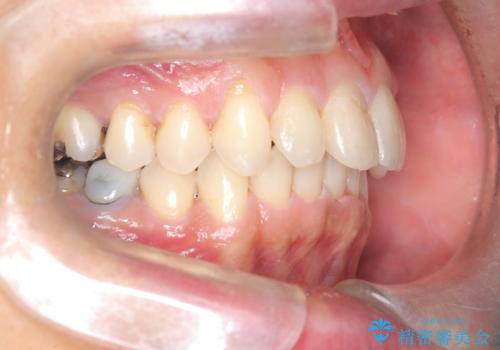

【遠心移動ワイヤー矯正】翼状捻転を治したい

- 前歯の捻れを主訴に来院されました。

今回は患者さんの希望もあり非抜歯にて歯列拡大、遠心移動を行なってできる限り前歯を下げながら配列する治療を行いました。

上顎はリンガルアーチにて遠心移動を行うことで前歯を唇側傾斜させずに配列することができました。